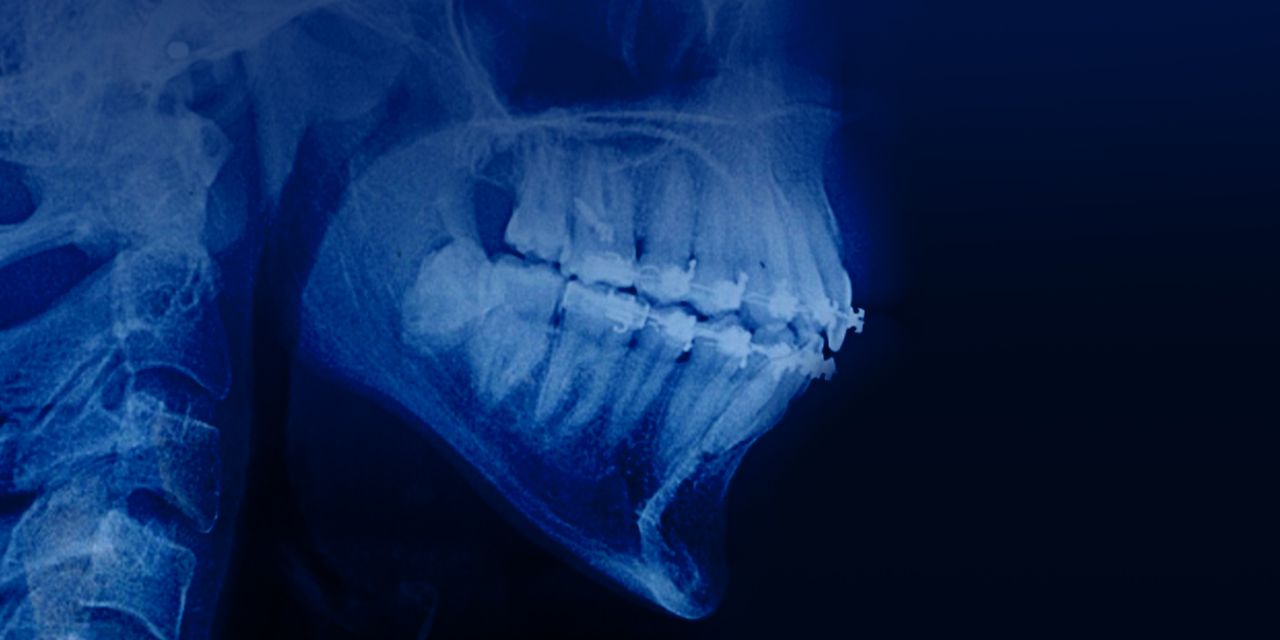

Ortodoncia en pacientes con patología periodontal y ósea

Nuevo curso online para ortodoncistas sobre cómo realizar un tratamiento de ortodoncia en pacientes con patología periodontal y ósea alveolar.

Dentro del curso se discutirá:

– Fuerzas ortodónticas ligeras al mover los dientes en pacientes adultos

– Creación del espacio previo a la implantación

– movimiento corporal de los dientes hacia un espacio de extracción

– Intrusión dental relativa y verdadera

– El uso de alineadores en pacientes adultos

– Uso del sistema Damon en pacientes adultos.